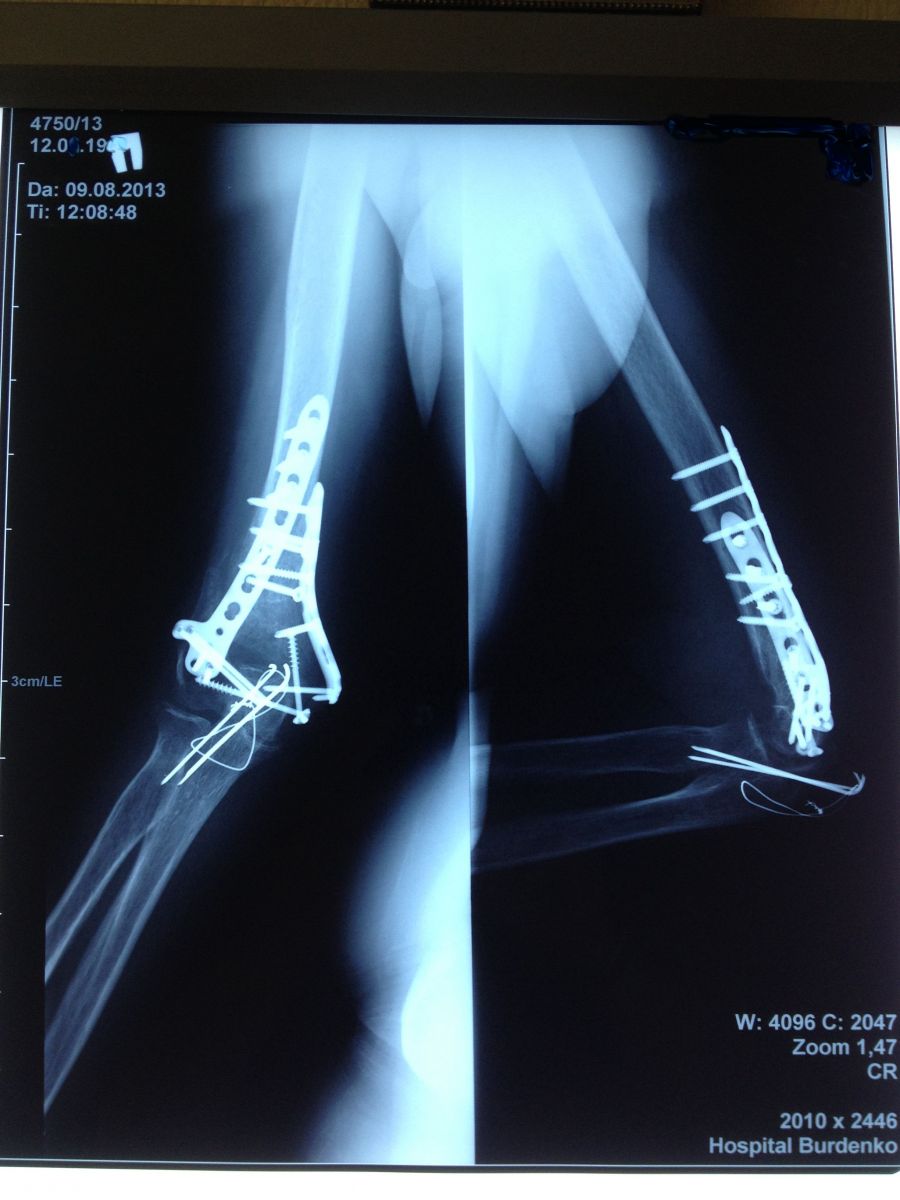

Рис.1. Пациентка, 52 года. Закрытый внутрисуставной оскольчатый перелом нижней трети правой плечевой кости со смещением костных отломков. Закрытый внутрисуставной перелом локтевого отростка правой локтевой кости со смещением костных отломков.

Рис.2. Пациентка, 52 года. Нижняя треть правой плечевой кости, фиксированная пластинами и винтами. Локтевой отросток правой локтевой кости, фиксированный спицами Киршнера и проволокой по Веберу.